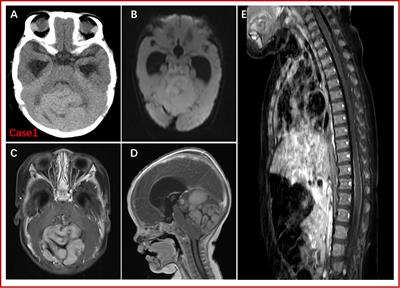

Congenital medulloblastoma in two brothers with SUFU-mutated Gorlin-Goltz syndrome: Case reports and literature review

Case Report